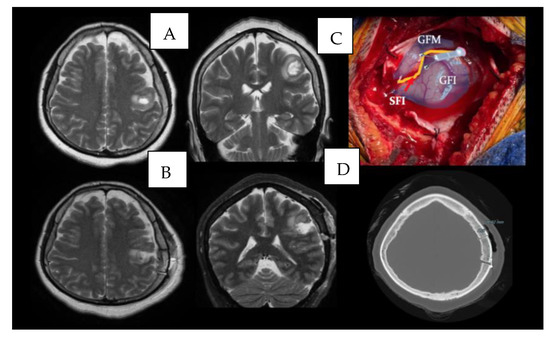

4.2. Case 2